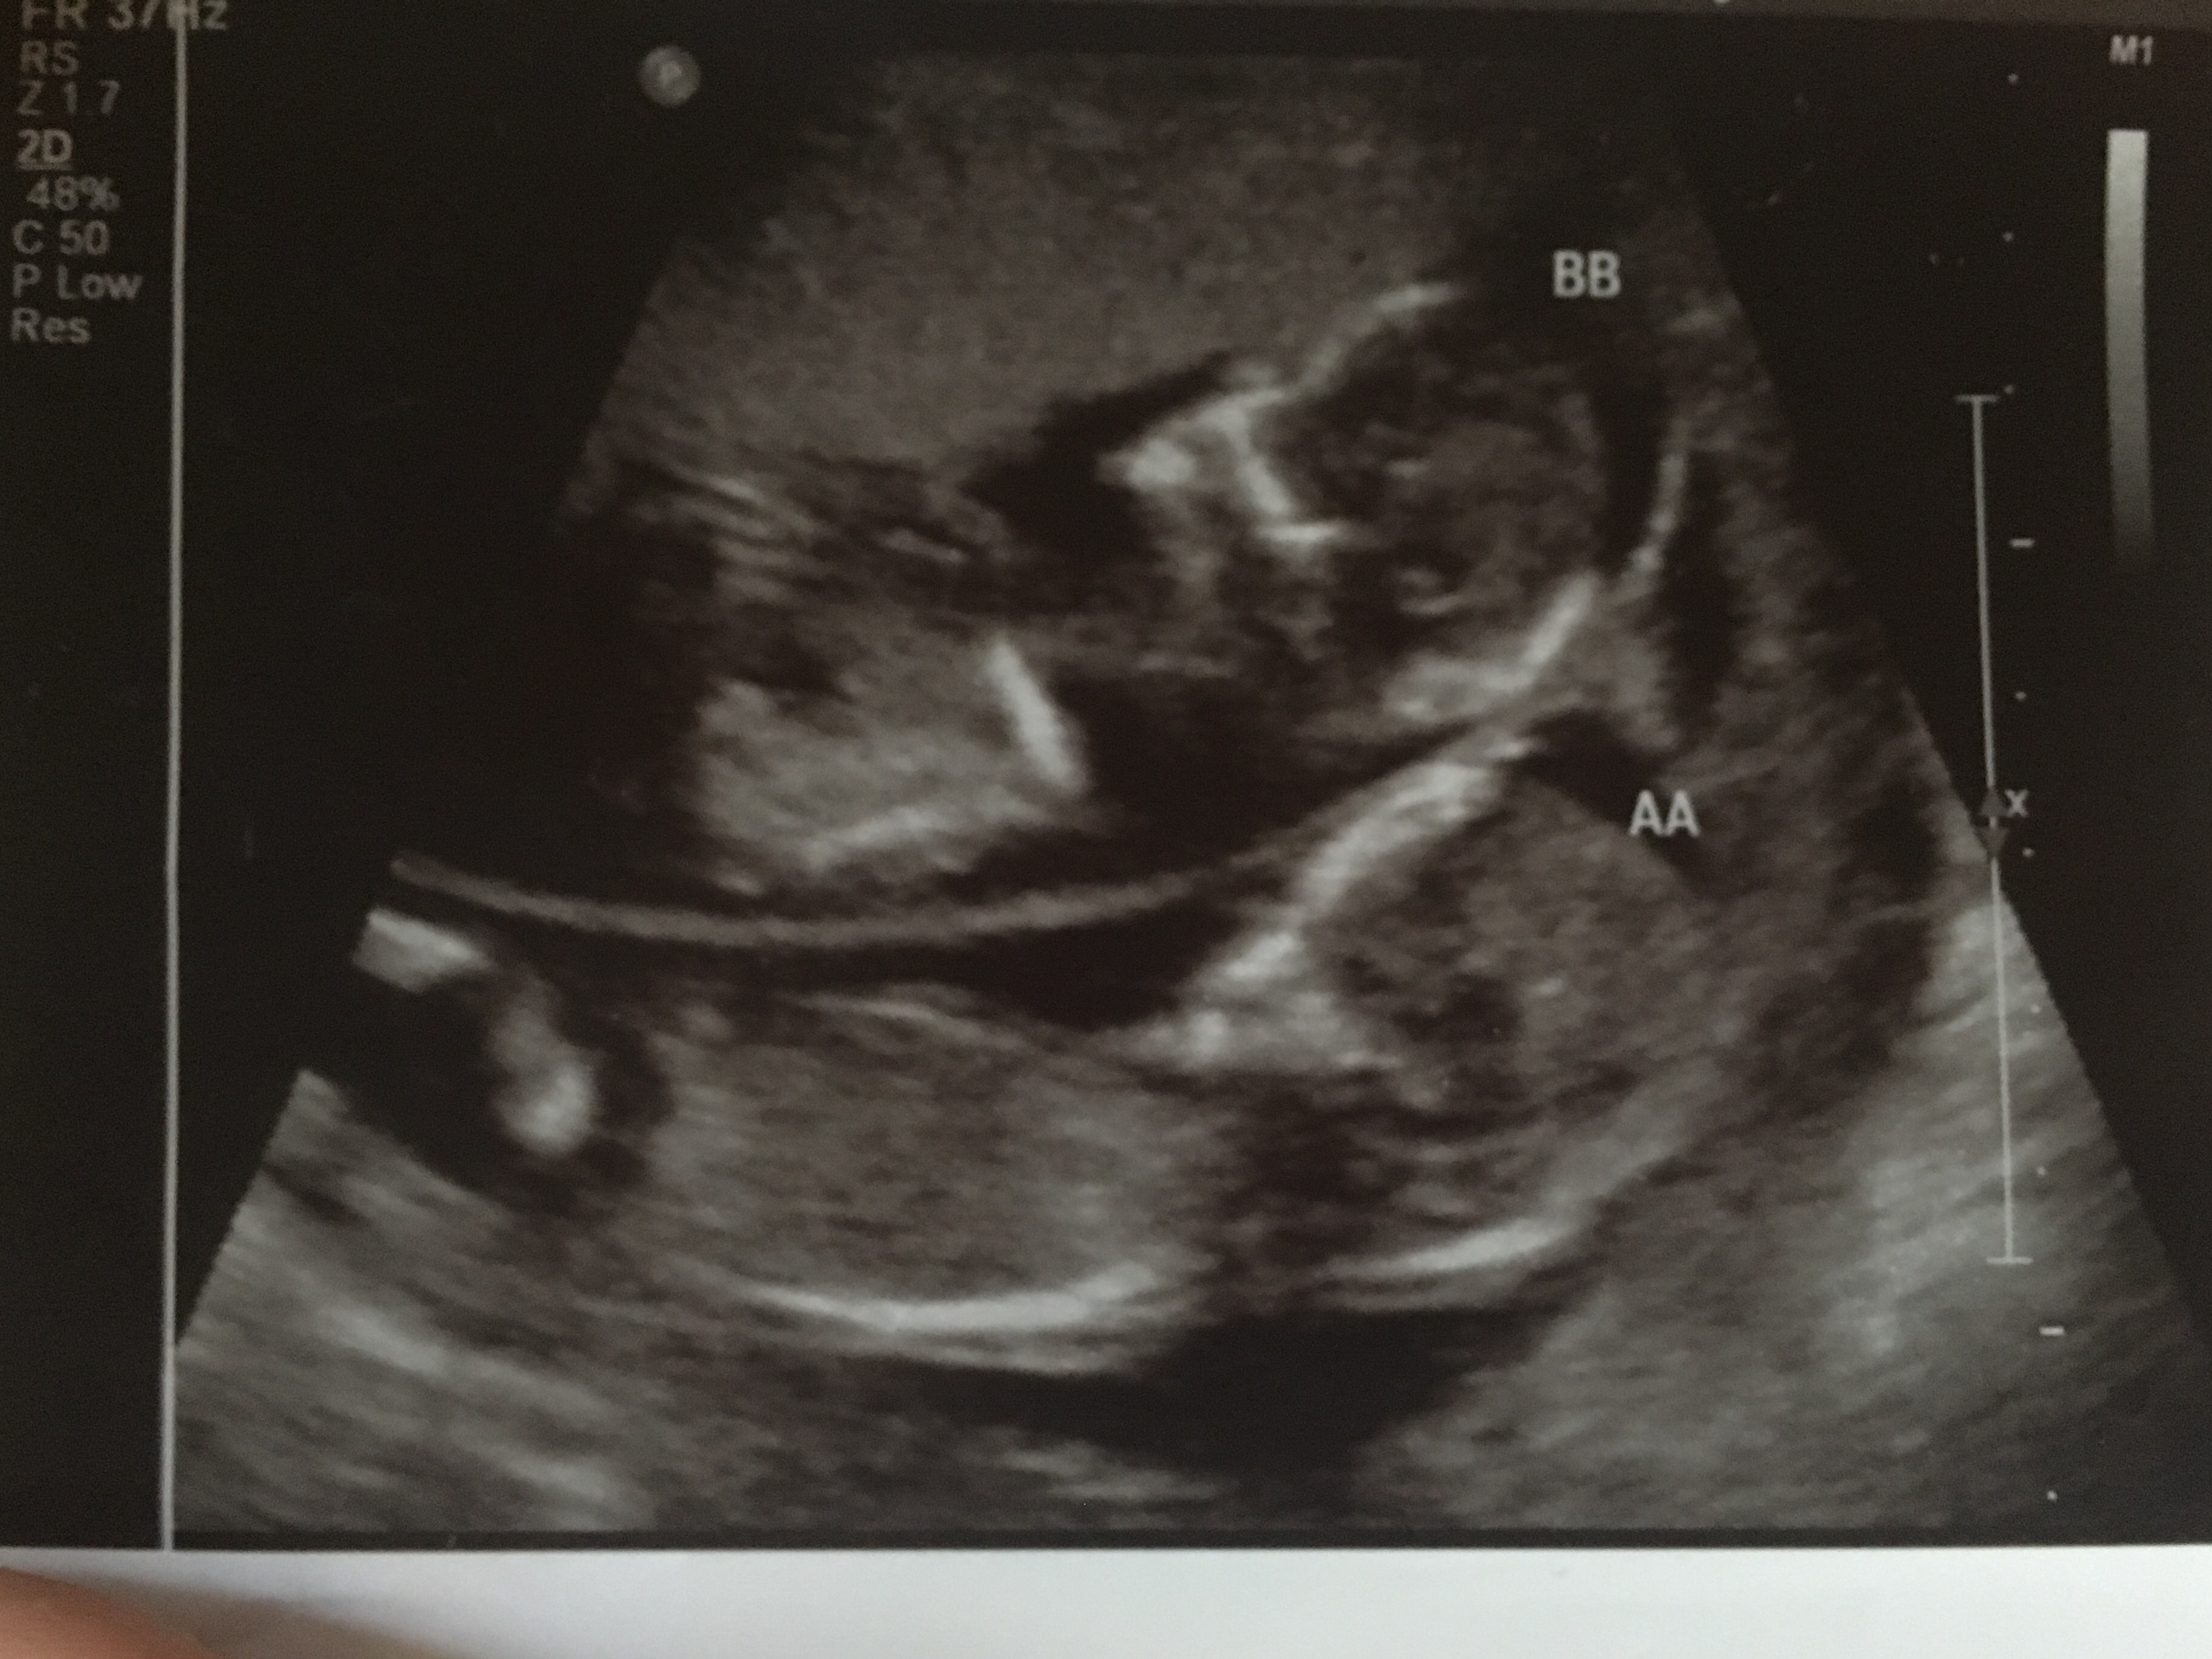

Any clues from my NT scan? twins at 13.5 weeks

Hi everyone! I'm obsessively staring at my NT scan pics hoping for clues. I have a daughter turning two soon and now we are expecting fraternal twins. I'm terrified because my hubby agreed to three children so I feel like this is my one and only shot to get a son and it's a done deal already! Of course I will be happy to have healthy daughters but I really wanted to experience the mother son relationship. Are front facing scans at all useful. I was looking at twin B and it seems there is some kind of nub there but I could be interpreting these scans wrong, probably desperately looking for some sign! I would really appreciate your opinions. Thank you.